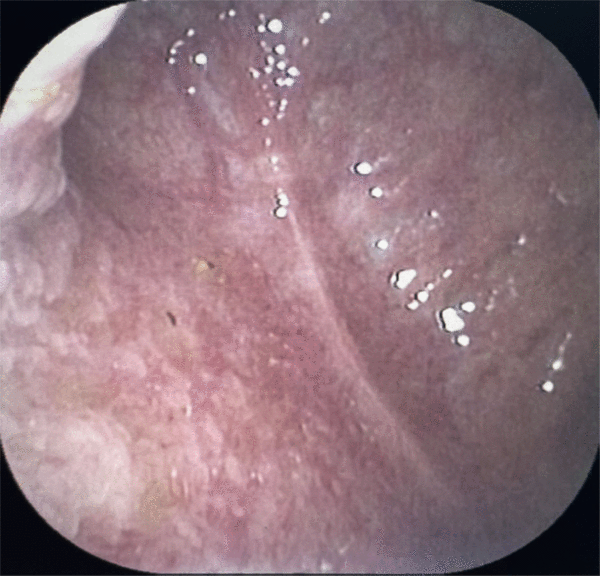

取完结石后的胆囊完好无损,又恢复健康